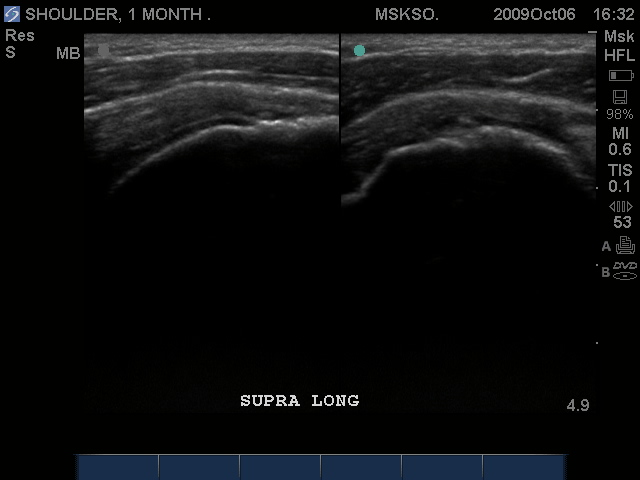

Supraspinatus tendon transverse over humeral head articular surface (articular surface changes in echotexture to hypoechoic)

"Cartilage Interface Sign" the hyperechoic rim over the hypoechoic articular cartilage is not usually seen unless a fluid layer is between the tendon and cartilage surface. When the tendon is resting normally over cartilage the interface is only hypoechoic.